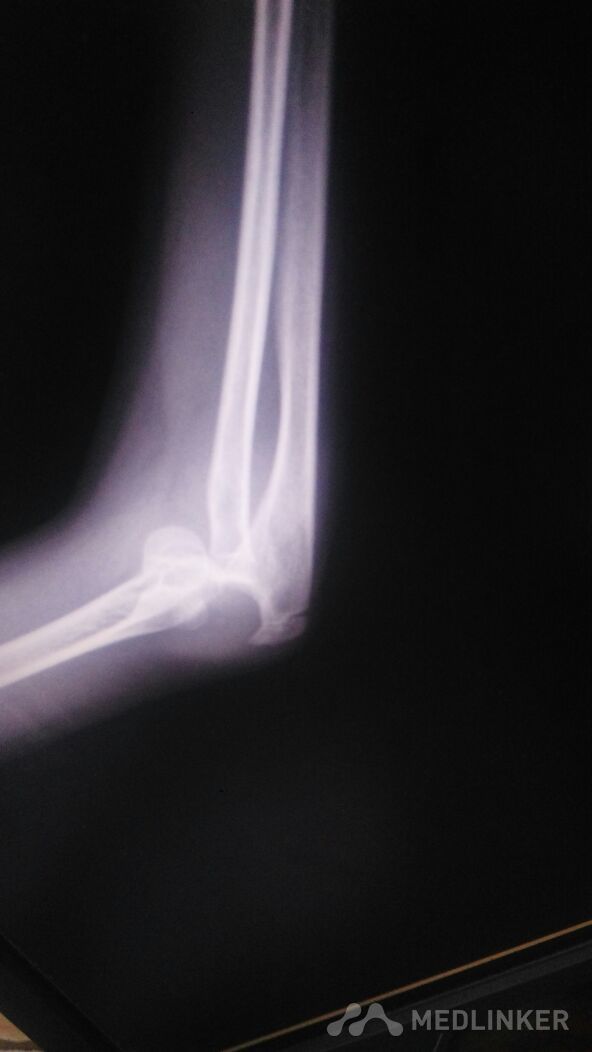

外伤后儿童的肘关节脱位。

左肘部肿痛畸形。以尺骨鹰嘴处为著,压痛阳性,叩痛阳性。左肘部活动受限。

骑自行车时摔倒致左肘部肿痛1小时。左肘部肿痛,畸形。活动受限。左手麻木。

左肘部脱位,后脱位,可以保守治疗。

肘关节肿胀明显。畸形明显。虽然脱位,韧带也有损伤。恢复有一定的时间。